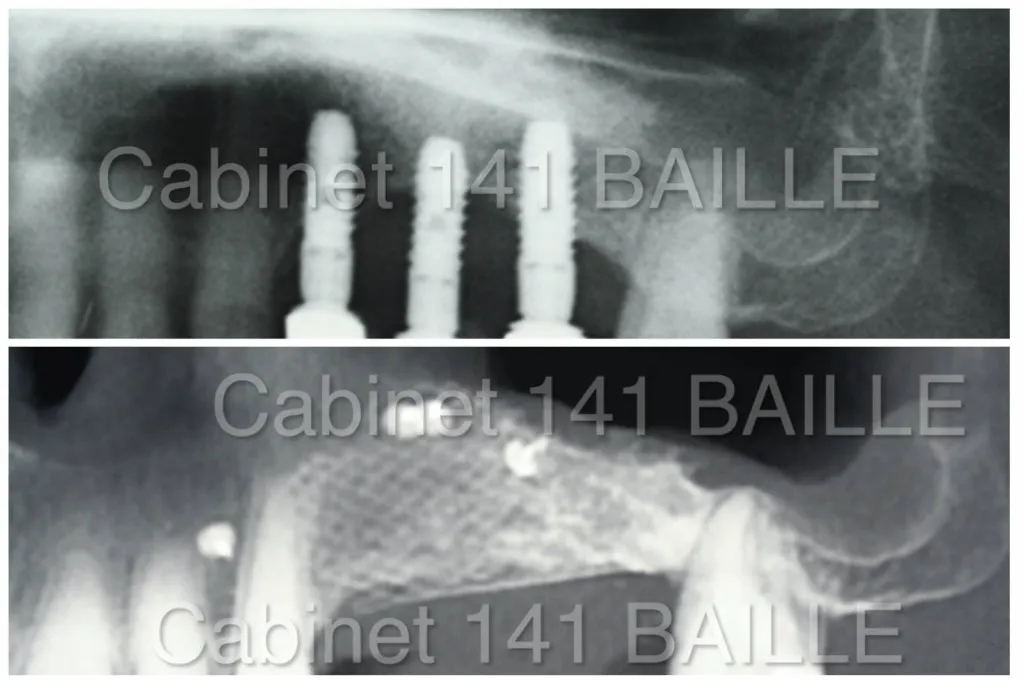

3. Régénération osseuse guidée

Actuellement les techniques de régénération osseuse guidée sont en voie de remplacer les techniques de greffe par biomatériaux.